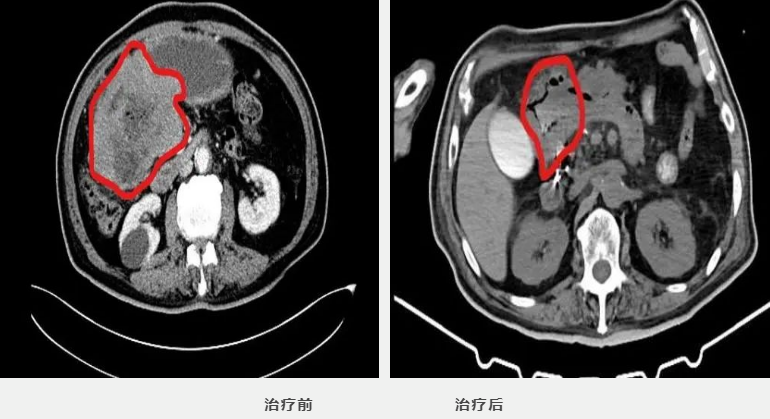

初见老杨,男,79岁,脸色苍白,气若游丝,面色萎靡地坐在轮椅上,一直以来间断腹部不适,既往有20年的糖尿病史,16年的脊髓炎一直双下肢行动不便,冠心病10余年,黄斑病变10年,一直被多种疾病缠绕,于我科恶性淋巴瘤化疗住院治疗,住院期间,老杨经历了人生的一波多折,次次都惊心动魄,终于最后战胜病魔,胜利出院。

住院第一折:今年1月初,老杨因间断出现上腹部不适,偶有进食后反酸、烧心及隐痛,伴乏力、消瘦,给予胃药效果不佳,2月做胃镜及病理提示:B细胞淋巴瘤,考虑粘膜相关性淋巴瘤,经抗HP治疗2周后症状无缓解,后就诊北京肿瘤医院病理会诊考虑:弥漫大B细胞淋巴瘤。入住肿瘤科,于3月21日积极进行第一周期R-miniCHOP治疗(患者老年,耐受性差),过程非常顺利。化疗用药第一关顺利通过。

人生短短数十载,老杨在这短短100余天内无数次与死神擦肩而过,无数次我们深入病窟,在时间紧迫,事态紧急情况下做出迅速有效的诊疗方案,过五关,斩六将,在抗癌以及化疗后出现各种的不可预知性的情况下,我们选择与兄弟科室联手斩杀病魔,并取得超出预期的效果,如今的老杨意气风发,生命体征平稳,并胜利出院,与家人团聚。并由衷感谢医务人员在黑暗中伸出的援助之手,感谢我们在最危急的时刻没有选择放弃,感谢我们一直以来的温暖与鼓励。